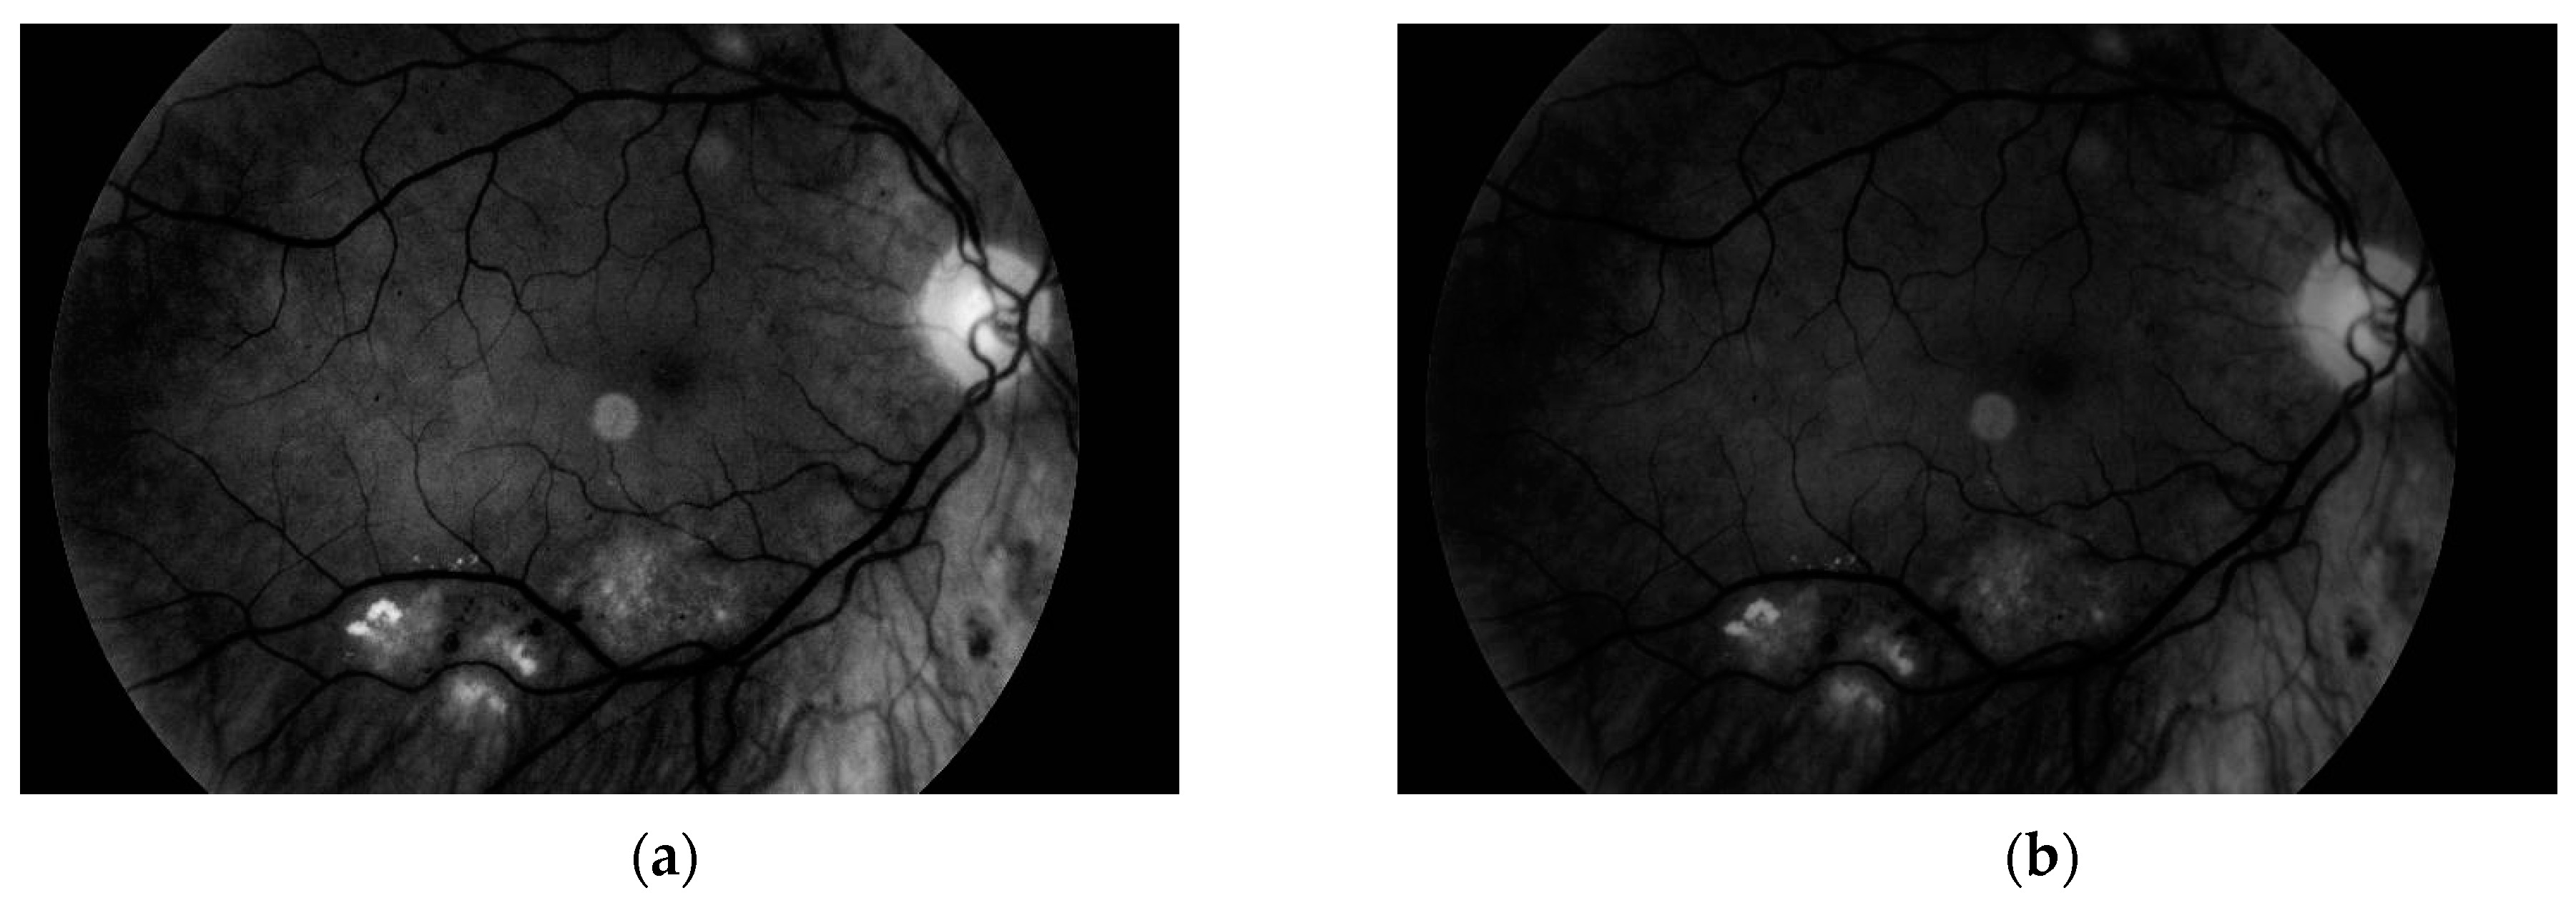

The second experiment was connected to checking whether our algorithm could be used for different images—ones with high resolution and high quality, and ones obtained by devices with worse parameters. Our database, obtained by the lower quality devices, contained 60 samples (50 healthy retinas and 10 with pathological changes). Thirty healthy samples were obtained with Digital Eye Center Microclear Handheld Ophthalmic Camera HNF whilst the rest of the low quality images were acquired with the d-Eye sensor. All of samples were acquired during medical examinations at Białystok University Clinical Hospital. Comparison was done to check if it was possible to observe pathological changes in retina images from worse devices. The sample image is presented in Figure 19.

The results showed that in the case of retina images from devices with lower precision, none of the healthy pictures was classified as a sample with pathological changes. Moreover, all retinas with diabetic retinopathy were classified as having pathological changes. This experiment confirmed that our solution can also be easily used with lower quality images. Moreover, it was pointed out that no additional adjustment of the proposed approach was needed.

Figure 19. Retina color image obtained by the device with worse parameters. No pathological changes exist.